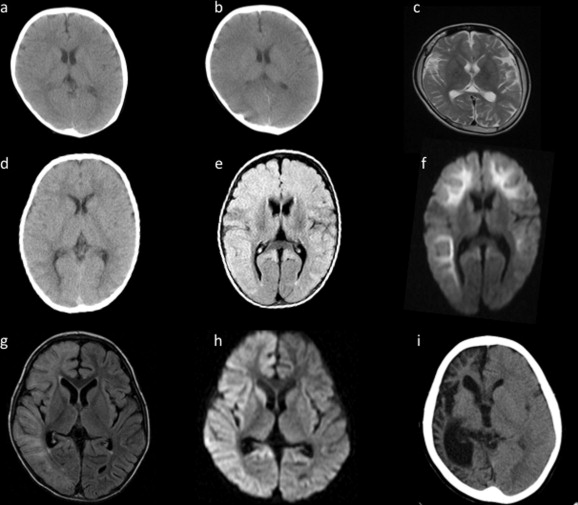

- компьютерная томография (КТ) и магнитно-резонансная томография (МРТ) головного мозга;

- компьютерная томография;

- МРТ и КТ.